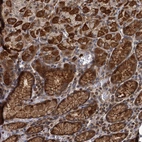

Immunohistochemical staining of human stomach shows strong cytoplasmic and membranous positivity in glandular cells.